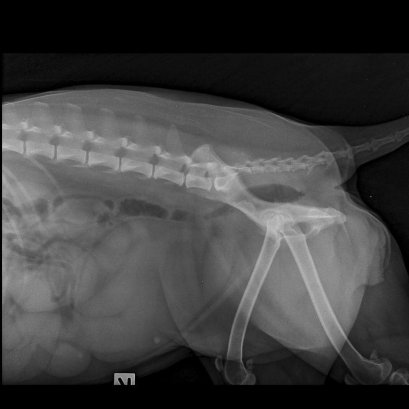

น้องน้อยหน่าเป็นสุนัขพันธุ์ไทยเพศเมียอายุเพียง 4 เดือน เจ้าของสังเกตว่าเริ่มมีอาการสองขาหลังอ่อนแรง โดยน้อยหน่ายังร่าเริงและทานอาหารได้ปกติ